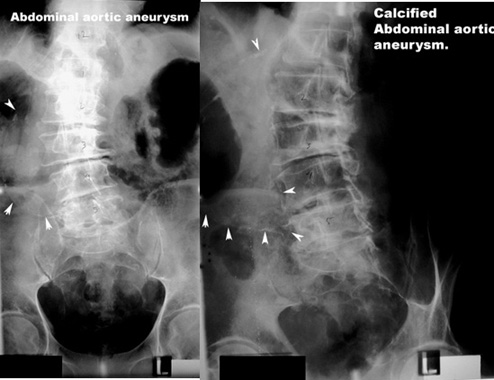

Plain film

Calcification of wall of aortic aneurysm

Calcification of wall of the aortic aneurysm